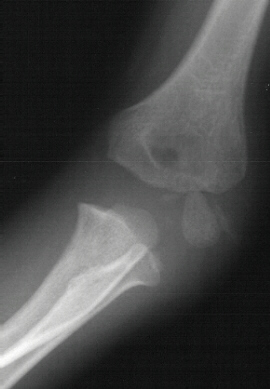

A five year and six month old white male sustained a fall

onto his outstretched right arm with immediate complaints of pain

and swelling in his right elbow. The child was unable to move

his arm secondary to pain. He was on the play ground and the fall

was not witnessed. Physical examination revealed swelling, tenderness

and crepitus over the lateral aspect of the elbow. The skin was

intact and neurovascular examination of the right upper extremity

was without deficits. The patient was taken to the operating room

where under general anesthesia and tourniquet control, the fracture

was exposed utilizing an anterolateral approach. Two diverging

k-wires were placed across the fracture site.